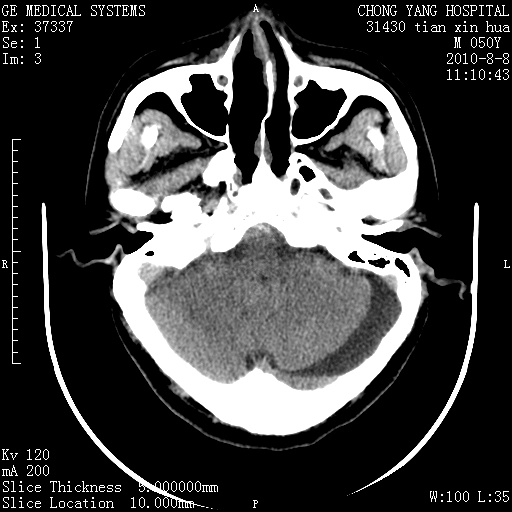

标题: CT28268:M50Y 头部外伤。 [打印本页]

标题: CT28268:M50Y 头部外伤。

考虑左侧枕部硬膜下积液。

乙状窦增宽,蛛网膜囊肿不除外

考虑左侧枕部蛛网膜囊肿;建议行mri检查。

病灶两端有脑膜尾征,考虑蛛网膜囊肿

枕骨稍变薄,脑组织有受压。首先考虑蛛网膜囊肿。